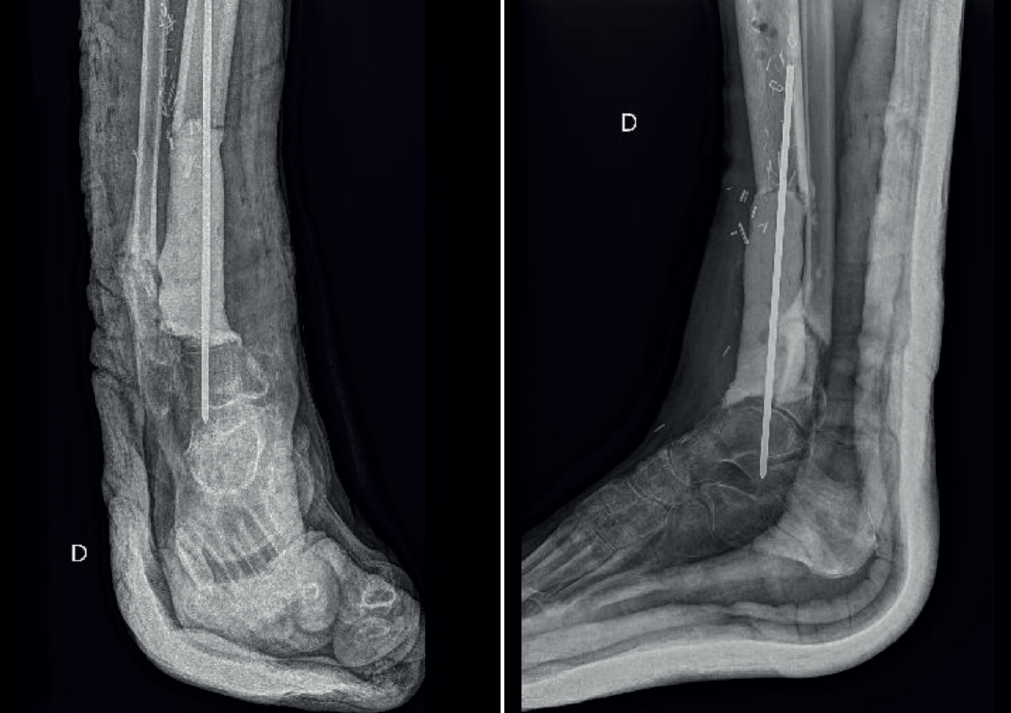

Tras la curación de la infección, siguiendo con la técnica de Masquelet, se realiza apertura de la membrana biológica, extracción del cemento y sustitución de este con injerto óseo esponjoso.

El gold standard para la obtención de este injerto óseo es la extracción de cresta ilíaca autóloga. Sin embargo, en este caso se utiliza el sistema RIA 2 (reamer irrigator aspirator), que consiste en un fresado del canal femoral con un dispositivo de fresado, irrigación y aspiración continua. Este aspirado se realiza de manera percutánea y a través del tendón rotuliano. Esta técnica según la bibliografía nos ofrece mayor volumen de extracción, menor morbilidad de la zona donante, mayor potencial biológico y similares resultados de consolidación que el gold standard(5).

Posteriormente, se estabiliza el miembro mediante un clavo retrógrado de artrodesis tibiotalocalcánea (Figura 8).

Se toman de nuevo muestras intraoperatorias que son positivas para para SEMS y Staphylococcus epidermidis resistente a la meticilina (SEMR), por lo que se pauta una antibioterapia con daptomicina i.v. durante 1 semana. Posteriormente, de manera ambulatoria será tratado con linezolid 600 mg cada 12 horas durante 6 a 8 semanas.

A los 6 meses tras la cirugía se observa consolidación completa del injerto en las radiografías, ausencia de síntomas de infección y normalización de la PCR y la VSG en las analíticas de control.

El paciente presenta una dismetría del miembro afectado de 25 mm (Figura 9) que se corrige con un alza.

Un año tras la cirugía, el paciente se encuentra bien, sin dolor en la pisada, no presenta signos ni síntomas de inflamación y las analíticas son normales (Figura 10). En las radiografías se observa consolidación completa (Figura 11).

Figura 8. Control radiológico postoperatorio del segundo tiempo quirúrgico. Aporte de injerto óseo y artrodesis tibiotalocalcánea mediante clavo retrógrado.